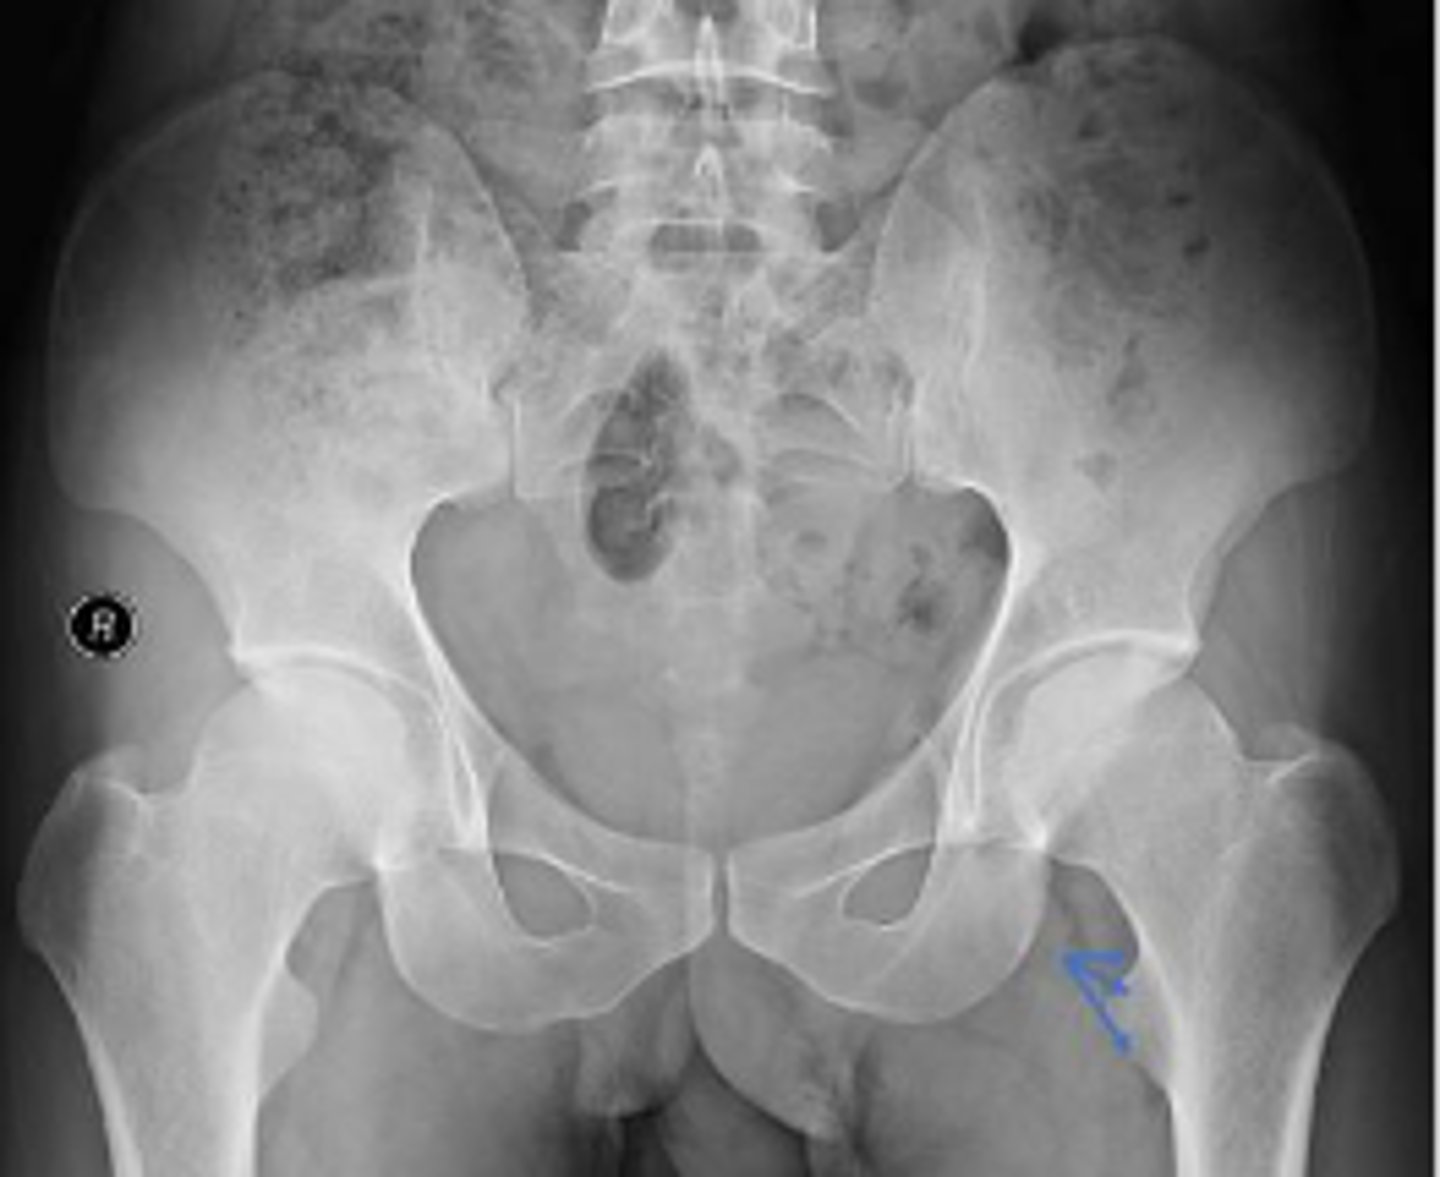

AP pelvis or bilateral hips

What is the name of the radiographic view?

Left ischial spine

What are the arrows pointing to?

Right sacroiliac joint

What joint space are the arrows pointing to?

Pubic symphysis

What joint space is the arrow pointing to?

PSIS

Lesser trochanter of the left femur

Left obturator foramen

Right pelvic teardrop

What is outlined?

Phleboliths

Greater trochanter of the right femur

Greater trochanter of the left femur